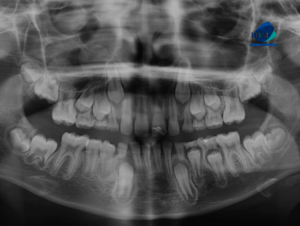

Paciente femenino de 39 años de edad, es referido al Instituto de Diagnóstico Maxilofacial – IDM para evaluación general.En la radiografía panorámica (Figura 1), se